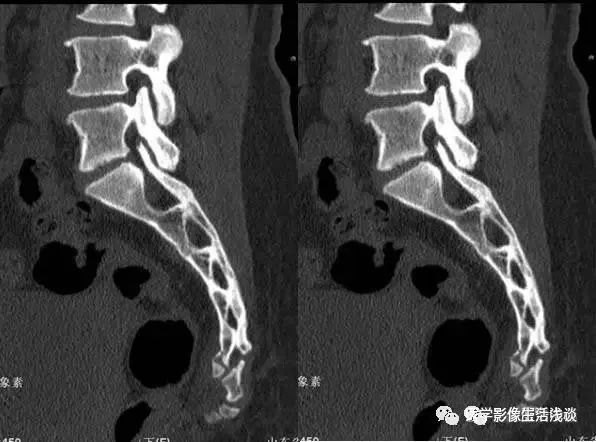

图1 均匀弯曲型;图2 骶骨成角型(骶3);图3 骶骨成角型(骶4-5);图4 骶骨成角型(骶5);图5尾骨成角型(尾1);图6 尾骨成角型(尾1-2);图7 尾骨成角型(尾2-3 );图8 尾骨脱位型;图9尾骨脱位型。

(3)尾骨向后滑移,也就文中所说的尾骨脱位型,常易误诊为尾骨脱位(见图8、9)。

病人女性,外伤后骶尾部疼痛,DR片示骶尾关节对应关系差,骶5椎体欠规则。CT重建示骶5椎体粉碎性骨折!

CT